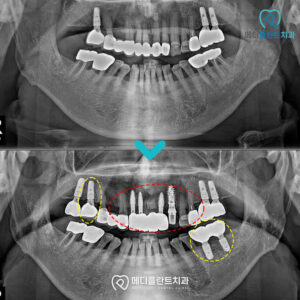

춘천수면치과, 임플란트 치료 과정이 두려워 미루고 있다면 . 안녕하세요 🙂 춘천수면치과 메디플란트치과입니다. . 치아에 문제가 생겨 불편하다면 일상생활에 큰 어려움이 발생할 수 있습니다. . 양치 자체도 불편하고 어렵기 때문에 치주…